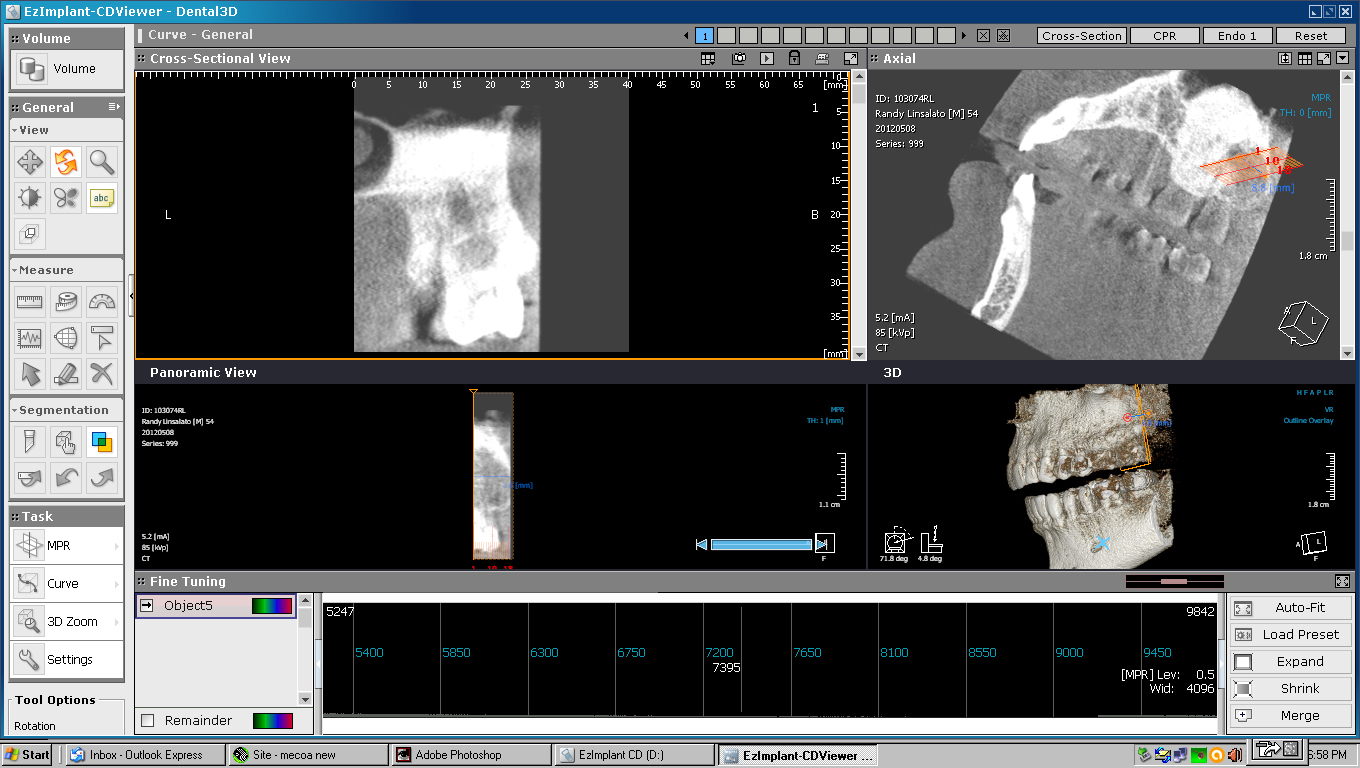

Bone loss in post treatment CT below

This comparison shows 14 and 15 taken by Fuentes prior to treatment 5-2012 on the left and 9-2016 on the right. Significant bone loss